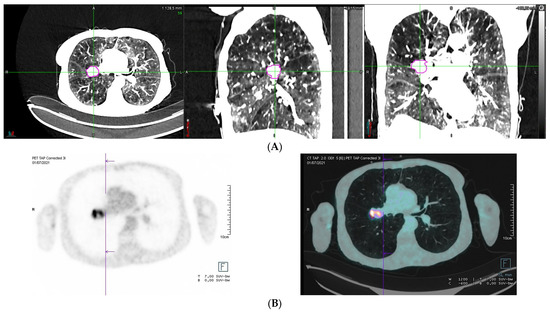

Lung Stereotactic Body Radiation Therapy in a Patient with Severe Lung Function Impairment Allowed by Gallium-68 Perfusion PET/CT Imaging: A Case Report

Lucia, F.; Hamya, M.; Pinot, F.; Bourhis, D.; Le Roux, P.-Y. Lung Stereotactic Body Radiation Therapy in a Patient with Severe Lung Function Impairment Allowed by Gallium-68 Perfusion PET/CT Imaging: A Case Report. Diagnostics 2023, 13, 718. https://doi.org/10.3390/diagnostics13040718